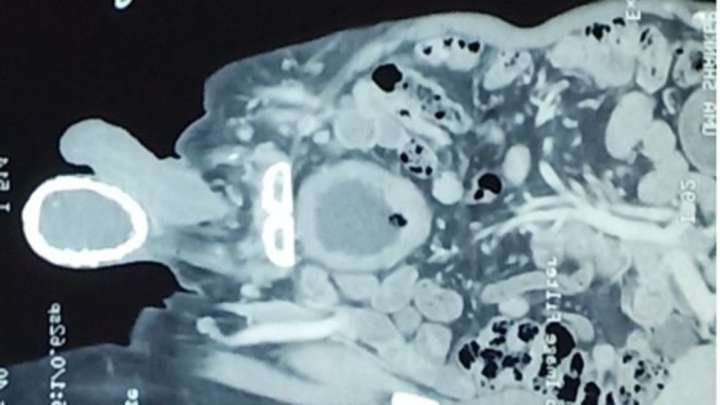

Según Crónica, profesionales de la salud lo sometieron a diversos estudios y los urólogos confimaron la dureza de sus testículos. A través de una tomografía, descubrieron que la razón detrás de la dureza era que padecía una infección conocida como hidrocele, una acumulación de líquido.

Luego, agregaron que ésta infección se combinó con calcificación, es decir, desarrolló una capa gruesa de calcio como si se tratara de una "cáscara de huevo". Detallaron que la infección que el hombre padecía se originó con la presencia de un parásito conocido como Wuchereria Bancrofti, común en zonas cálidas y tropicales, que se transmite a través de los mosquitos.